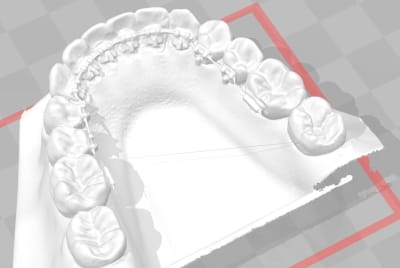

Et mon premier cas ou j'ai commencé par coller les bracket sur le modéle en plâtre, puis j'ai scanner pour faire le set up final avec les bracket.

Très sympa pour plier le fil et la réalisation du set up ma montré que même en positionnant les brackets en indirect, à la fin du set up le fil n'est pas droit. L'avantage c'est que plier le fil n'est pas très compliqué sur un model 3D.

Et mon hopital vient de recevoir les 2 scanner intra oral dental wing, j'en ai essayé un en vitesse au labo sur un modéle en plâtre et ça semble sympa ( mais une empreinte aliginate c'est quand même plus rapide ) . J'en teste un demain sur un patient qui à déjà les 2D en bouche.